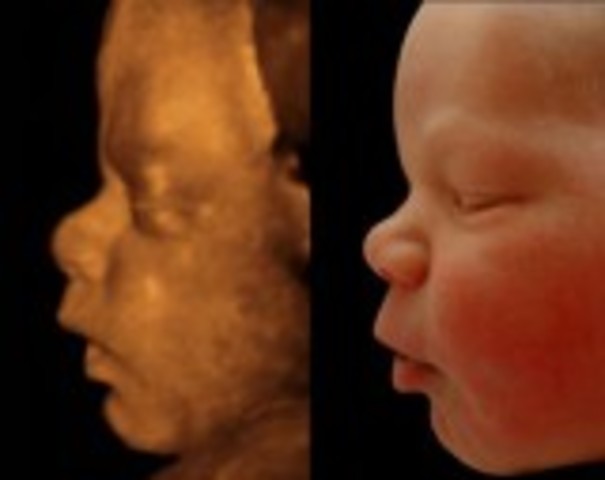

• Week 24: Breathing

Week 24: Breathing

By this week, the baby is 12 inches long and weighs 1.3 pounds. The baby is now practicing how to breathe since branches of the respiratory tree are forming in its lungs. It is currently being covered by hair. The baby is beginning to look like an actual baby with increasing facial features.